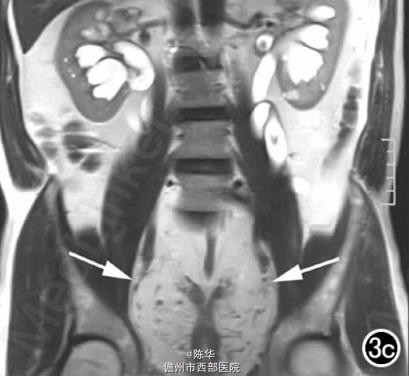

腹部B超示双肾增大,双肾慢性肾病声像;双肾中度积液伴双输尿管上段扩张。 IVPshi双侧输尿管中或下段梗阻。 膀胱造影:经尿道置管后,注射对比剂充盈膀胱,膀胱下半部先充盈,继续灌注对比剂后见膀胱完全显影,膀胱形态异常,呈“倒葫芦状”(图1)。 CT增强扫描行延迟期 MPR重组,见双侧肾盂、肾盏扩张积液;双侧输尿管纡曲、扩张,下端呈鸟嘴样变窄;膀胱变形、体积减小(图2); MRI平扫示双侧肾盂、肾盏扩张积液,双侧输尿管扩张并下端鸟嘴样变窄,盆腔内多量脂肪沉积,分布于膀胱、直肠周围,T1WI、T2WI呈明显高信号,T2WI抑脂像呈稍高信号,膀胱受压变形、体积减小(图3a~c); MRU示双侧肾盂肾盏扩张、积液,双侧输尿管显著纡曲、扩张,下端鸟嘴样变窄,管壁光整,膀胱变形、体积较小、位置抬高(图3d)。